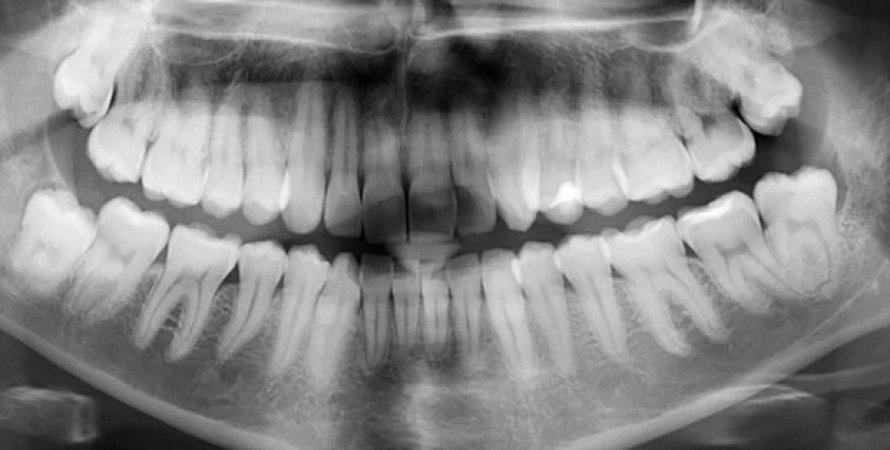

Рентгенівський знімок зуби

Фото: ScienceAlert